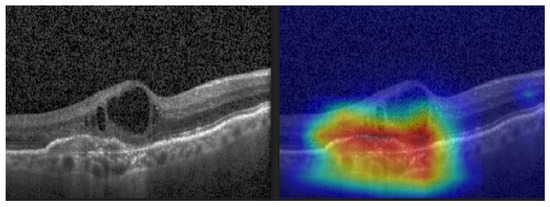

Gradient-weighted Class Activation Mapping (Grad-CAM) (see Figure 12) was also performed to visually confirm the performance of our CNN model in the most significant regions in the OCT image [35,42,43,44].

Figure 12.

CNV and its Grad-CAM.